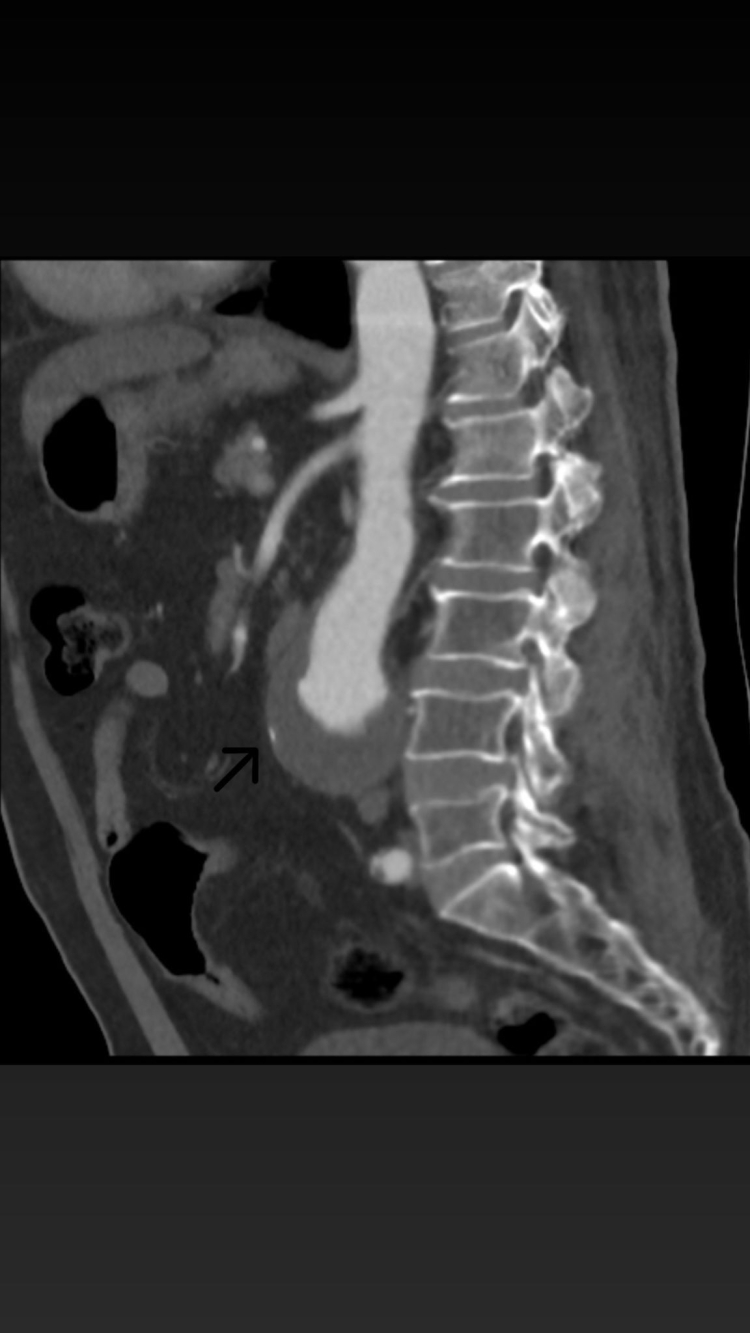

Karın aort anevrizması, vücudun en büyük atardamarı olan aortun karın bölgesindeki kısmının anormal şekilde genişlemesidir. Kontrol altına alınmadığında, bu genişleme yırtılma (diseksiyon) riskini beraberinde getirir ki bu da hayati tehlike taşıyan bir durumdur. Hastanın aort damarındaki genişlemenin 56 mm'ye ulaşması üzerine, bu potansiyel patlama riskini ortadan kaldırmak amacıyla EVAR prosedürü uygulandı.

Ameliyat, hastanın kasıklarından yapılan küçük kesiler aracılığıyla gerçekleştirildi. Bu minimal invaziv yöntemle, balonlaşan damarın içine özel bir greft kaplı stent yerleştirilerek, anevrizmatik bölge izole edildi ve damarın normal çapına dönmesi sağlandı.